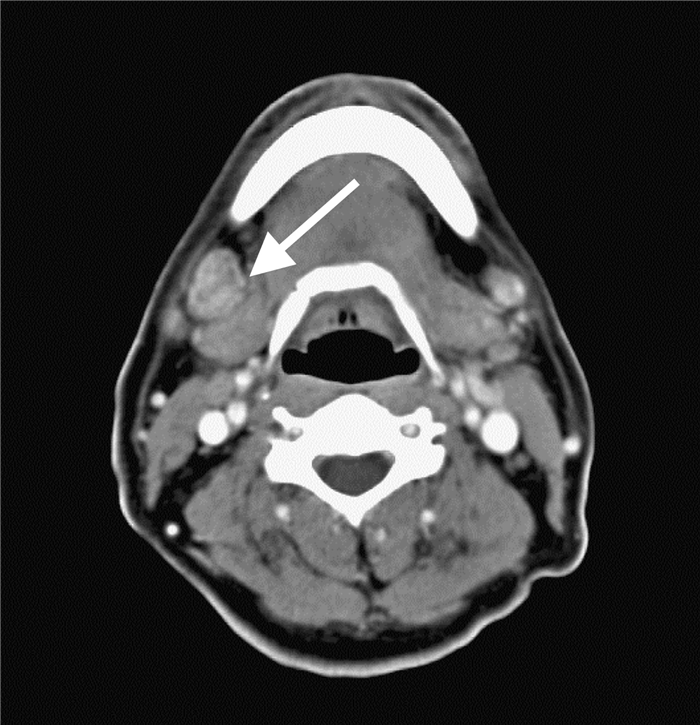

На ниже представленном постконтрастном КТ снимке представлен пациент с карциномой языка и лимфаденопатией II группы лимфатических узлов.

На ниже представленном постконтрастном КТ изображении визуализируется увеличение и контрастное усиление лимфатических узлов III группы.